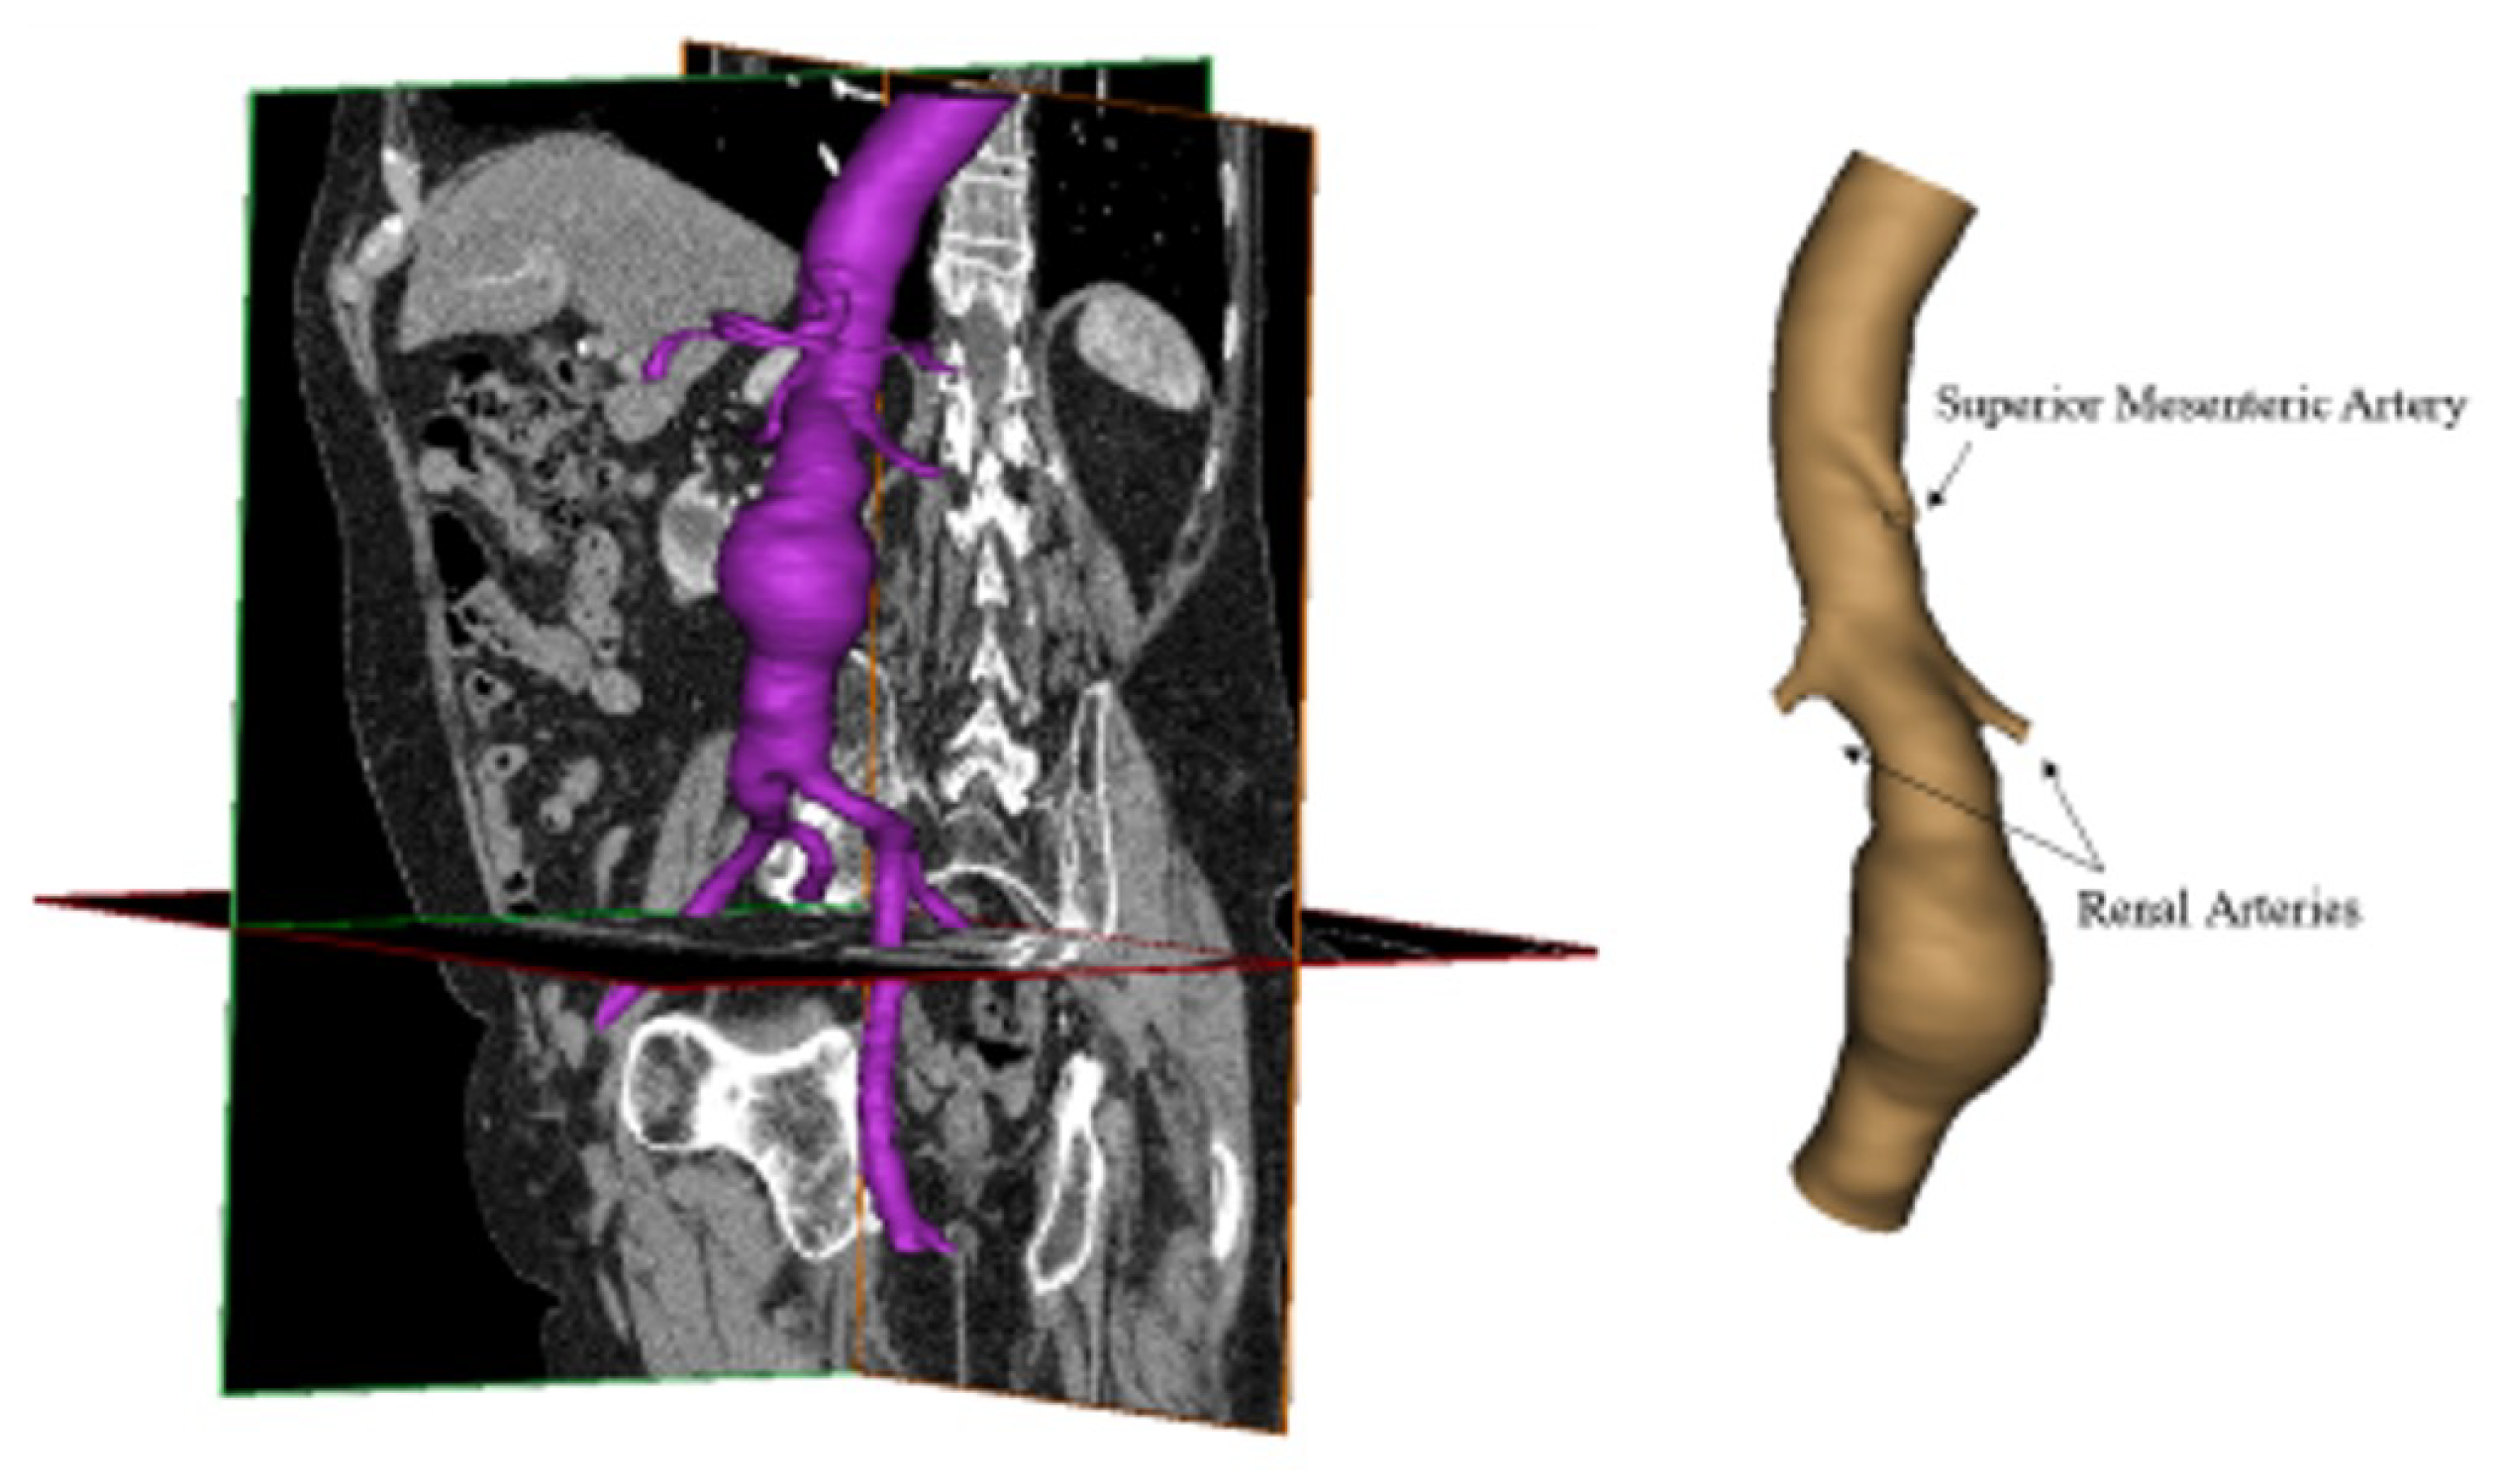

2. Materials and Methods